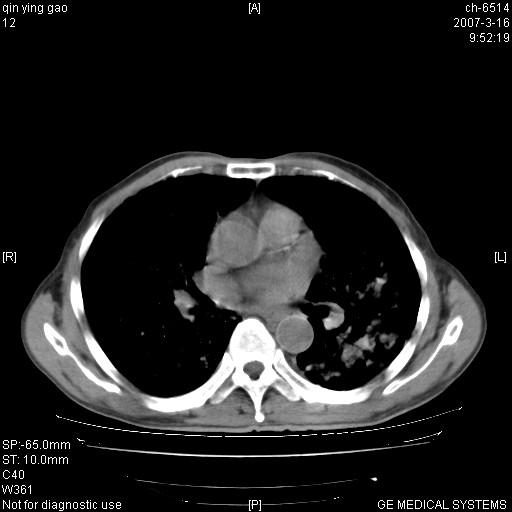

男,64岁.乏力2个月,畏寒、发热1月余。体重下降。血沉加快,白细胞不高。

双肺以中上肺野为著斑片状.结节壮密度增高影 左上肺前段可见小类圆钙化灶 纵隔淋巴结无明显肿大

3.主动脉弓.冠状动脉钙化形成

双肺以中上肺野为著斑片状.结节壮密度增高影,纵隔淋巴结无明显肿大。考虑:

1、肺结核。

2、主动脉、冠状动脉硬化。

病变以两肺上野为著,部分病灶有钙化,纵隔窗显示病灶有新老不一,这个首先和结核脱不了干系,还有部分病灶有融洽的倾向,肿瘤也不能完全排出